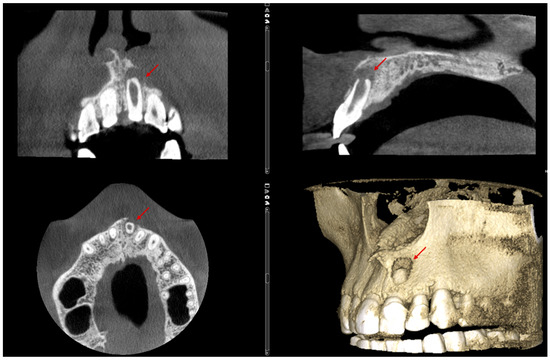

The CBCT scan revealed a labial cortical bone defect associated with tooth #21, measuring approximately 7 mm in diameter. The apical third of the root was uncovered by bone; an apical bone fenestration was present. The palatal cortical bone remained intact and was not affected by the periapical pathology (Figure 3). According to the CBCT Periapical Index (CBCTPAI), the lesion was classified as score 4 + D, indicating extensive periapical radiolucency with destruction of the cortical bone [9].

Figure 3.

The labial bone fenestration is visible on the CBCT image (indicated by red arrows).

The patient returned for a follow-up visit two years later. The tooth was asymptomatic, and the radiograph showed no signs of periapical radiolucency (Figure 5a). The caries lesion on the mesial surface was treated. Eight months later, a new CBCT scan was performed by another dentist due to a traumatic injury on the right side of the jaw. Upon reviewing the scan, valuable diagnostic information became apparent, including complete restoration of the cortical bone, reestablishment of healthy periapical tissues, and the absence of any radiolucency around the apex of tooth #21. The CBCT PAI score was recorded as 0, indicating complete healing (Figure 5b,c).

Figure 5.

Complete regeneration of the apical bone fenestration observed over a period of two years and eight months: (a) periapical radiograph showing resolution of the periapical radiolucency; (b) CBCT scan confirming re-establishment of the cortical bone and healthy periapical tissues; (c) the 3D reconstruction is included to illustrate the anatomical changes before and after treatment.